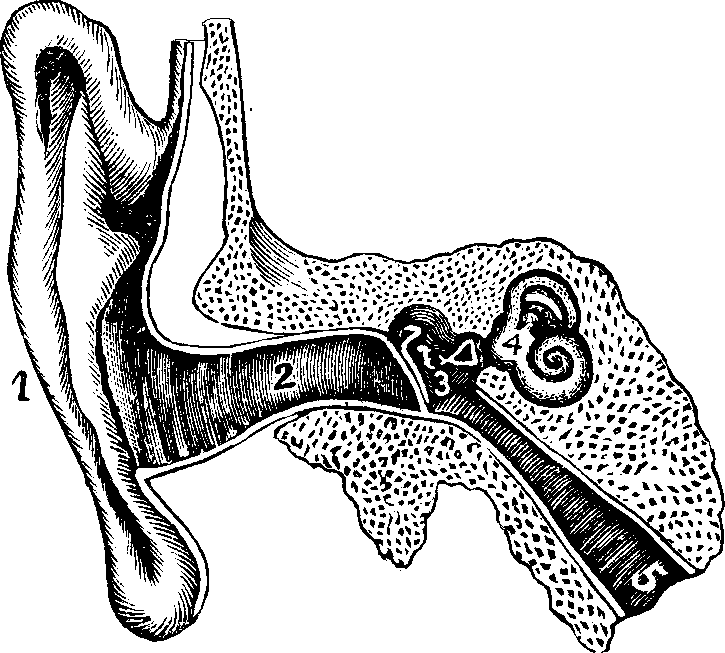

and meeting in the middle line, they entirely prevent the passage of any

fluid which may be forced along the artery towards the heart, but, flapping

back, they offer no obstruction to the free flow of blood from the

ventricles into the arteries.

Fig. 42. A representation of